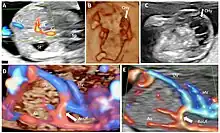

Doppler echocardiography is the use of Doppler ultrasonography to examine the heart.[13] An echocardiogram can, within certain limits, produce an accurate assessment of the direction of blood flow and the velocity of blood and cardiac tissue at any arbitrary point using the Doppler effect. One of the limitations is that the ultrasound beam should be as parallel to the blood flow as possible. Velocity measurements allow assessment of cardiac valve areas and function, any abnormal communications between the left and right side of the heart, any leaking of blood through the valves (valvular regurgitation), calculation of the cardiac output and calculation of E/A ratio[14] (a measure of diastolic dysfunction). Contrast-enhanced ultrasound using gas-filled microbubble contrast media can be used to improve velocity or other flow-related medical measurements.